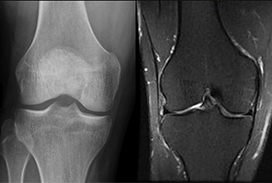

2023 London Imaging Discovery Day